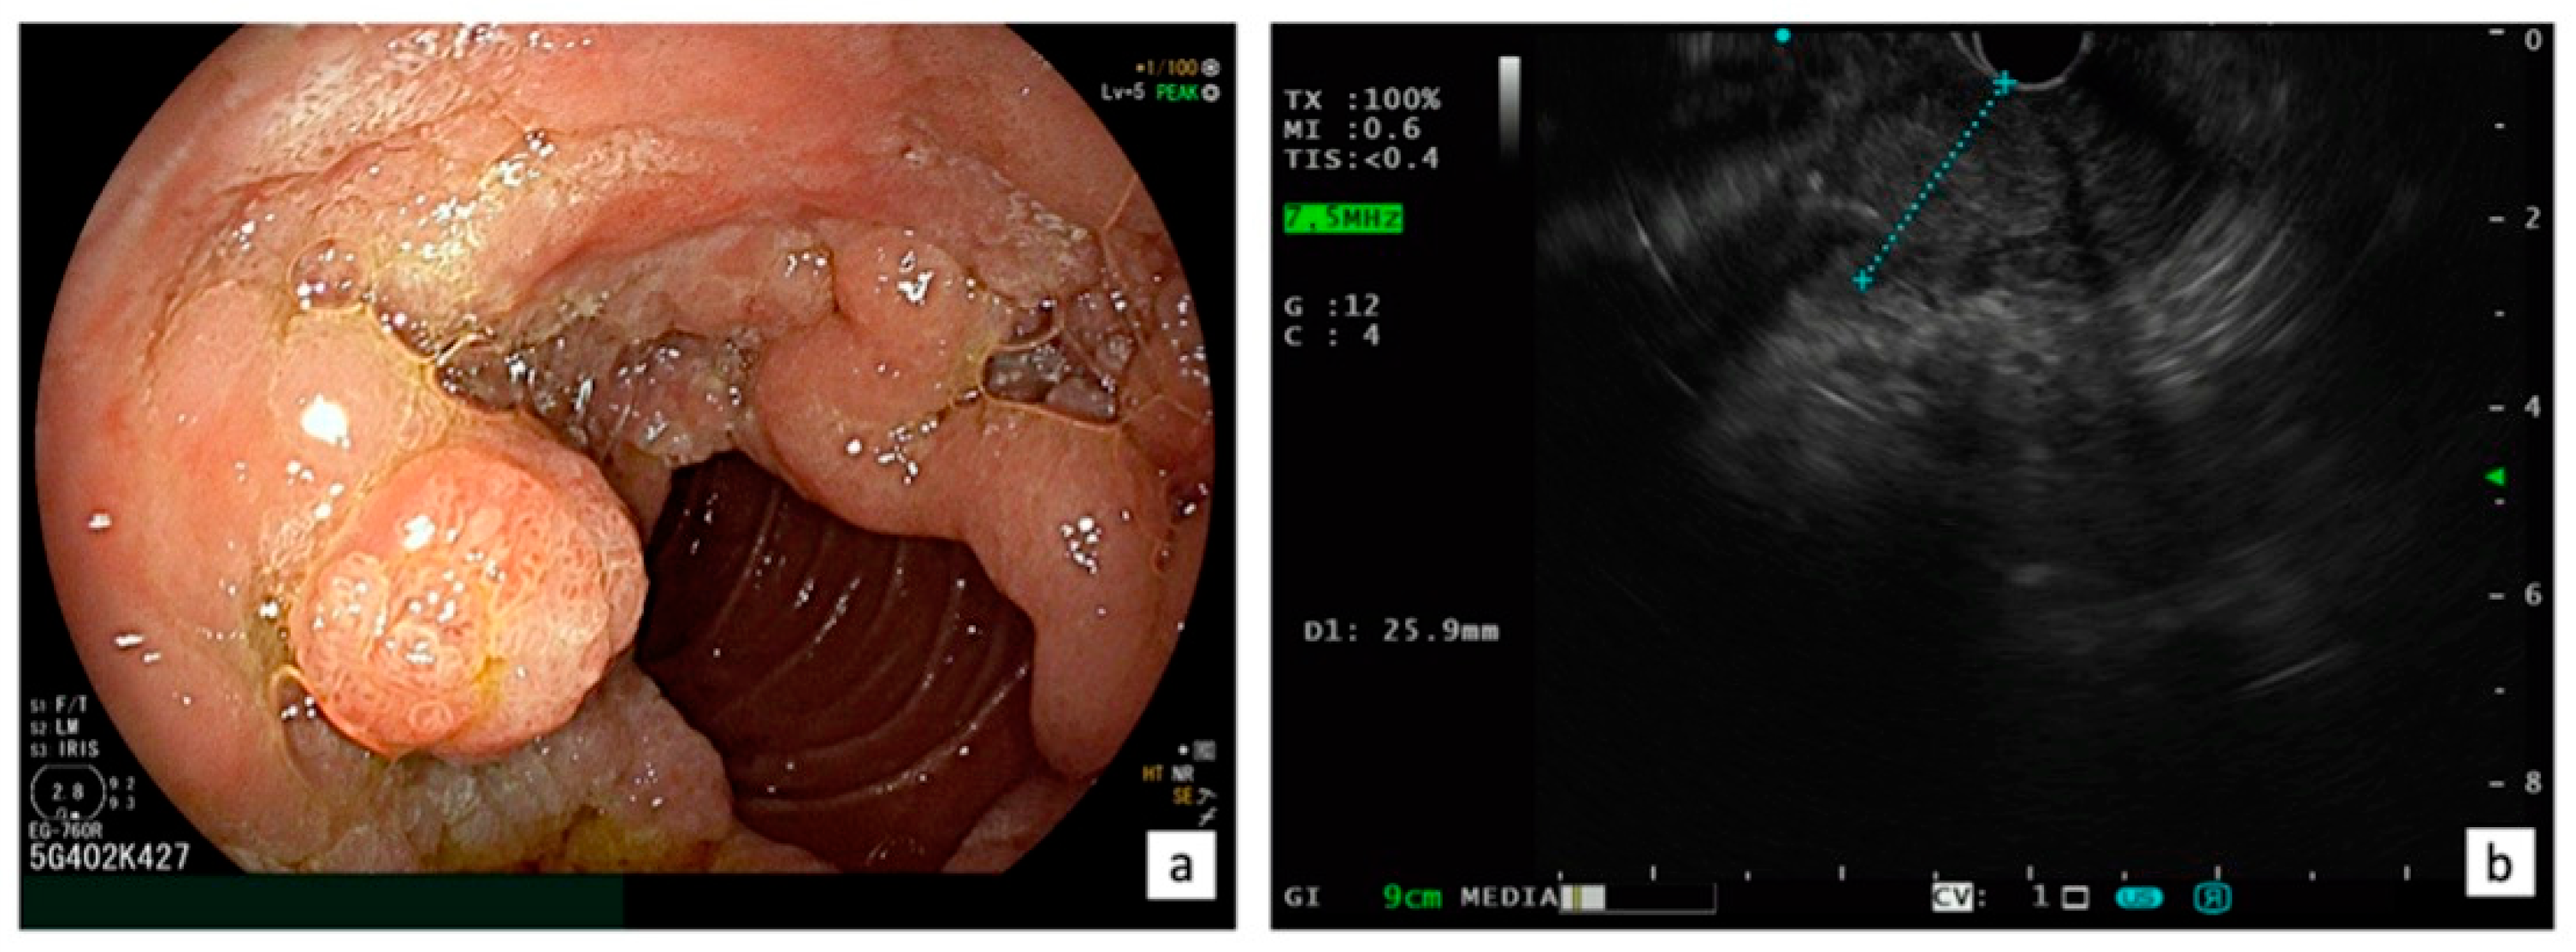

Figure 3.

Indication for surgical treatment: LST-p characterized with a circumferential extra-papillary component on the duodenal wall with a tumor size exceeding 4 cm (a) and an intraductal involvement >20 mm confirmed using EUS (b).

Presently, there is a lack of RCTs that compare EP and surgical treatments, such as transduodenal ampullectomy or pancreaticoduodenectomy, for ANLs. In a recent systematic review and meta-analysis, including a total of 39 studies with 1753 patients (1468 EP and 285 transduodenal ampullectomy), Garg et al. [75] aimed to compare long-term recurrence of benign sporadic ANLs after EP and transduodenal ampullectomy, showing that endoscopic and surgical ampullectomy have similar recurrence rates at 1, 2, 3, and 5 years of follow-up. Thus, when feasible, EP is considered the first choice for ANL. However, there are still situations where surgery remains a viable option for ANL, including the following: (1) intraductal involvement (>20 mm); (2) technical limitations (the presence of a diverticulum or the tumor size exceeding 4 cm); (3) incomplete resection after EP (positive margins); and (4) local recurrence not endoscopically treatable [76] (Figure 3). A systematic review, which included five retrospective cohort studies with 466 patients, revealed that surgical resection (transduodenal ampullectomy or pancreaticoduodenectomy) had better outcomes in achieving complete resection of ANLs compared to EP (risk difference [RD] −0.37, 95% CI −0.50 to −0.24, p < 0.001, I 2 = 71%) without any difference in complications [77]. However, when utilizing a fixed effects model, EP exhibited a lower rate of adverse events (RD −0.28, 95% CI −0.39 to −0.18, p < 0.001; I 2 = 95%) [77].